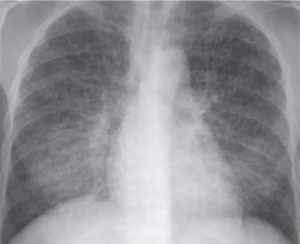

Pleural effusion is usually unilateral and due to subpleural infection.

Pleural effusions are more common in adults with primary tuberculosis (40%).